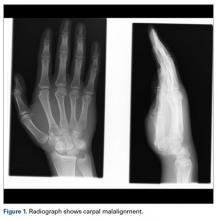

A fit and healthy 30-year-old male software professional fell down stairs, landed on his nondominant right hand, and sustained a high-energy wrist injury. The patient also sustained a concussion, without focal neurologic deficit, and was unable to recall the exact mechanism of the wrist injury (there were no other witnesses). Radiographs of the right wrist in the emergency department showed only a nondisplaced fracture of the neck of the second, third, fourth, and fifth metacarpals and a nondisplaced fracture of the radial styloid.

Later, however, the hand surgery team evaluated the radiograph as well as computed tomography (CT) scans and found a translunate, transradial, transtriquetral, transtrapezoid perilunate dislocation of the wrist with multiple metacarpal neck fractures ( Figures 1-5 ).The next day, with the patient under general anesthesia, an attempt to reduce the perilunate dislocation by manipulation was unsuccessful. Open reduction and internal fixation (ORIF) were performed through a dorsal approach; the perilunate dislocation was reduced and stabilized with lunocapitate 1.2-mm Kirschner wire (K-wire). The scapholunate and lunotriquetral ligaments were found to be intact, and the significantly displaced triquetral fracture was treated with internal fixation involving 2 minifragment screws ( Figure 6 ).